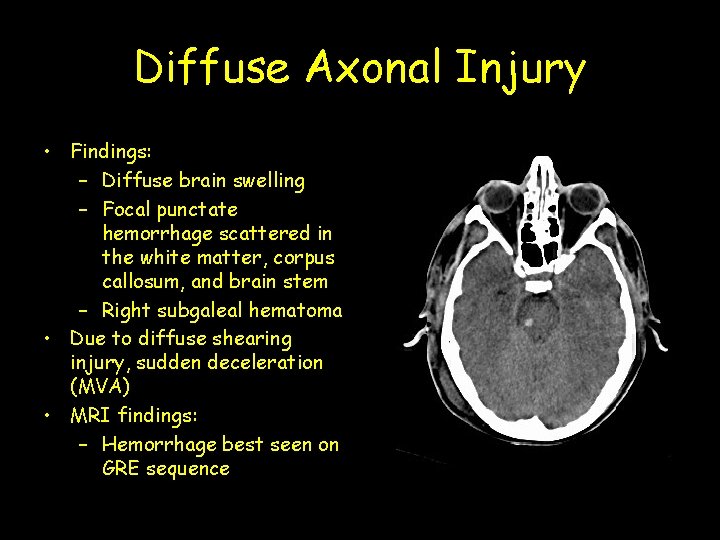

Diffuse Axonal Injury • Findings: – Diffuse brain swelling – Focal punctate hemorrhage scattered in the white matter, corpus callosum, and brain stem – Right subgaleal hematoma • Due to diffuse shearing injury, sudden deceleration (MVA) • MRI findings: – Hemorrhage best seen on GRE sequence